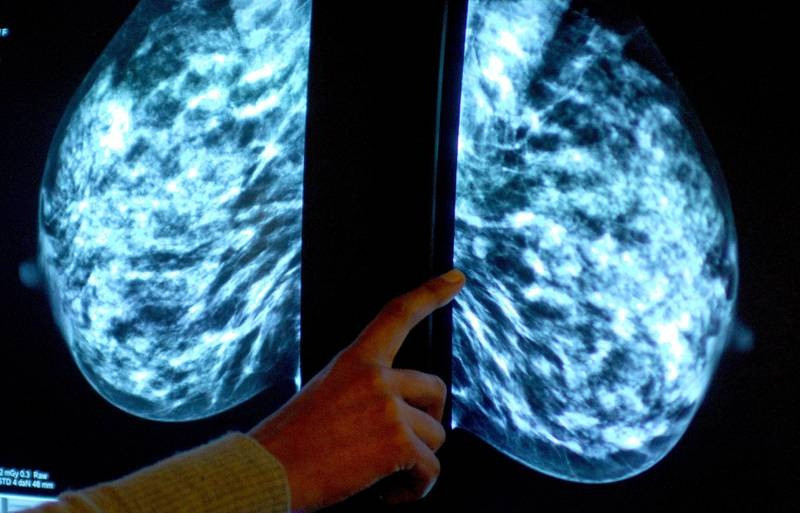

Nghiên cứu chủ yếu tập trung vào những bệnh nhân được chẩn đoán mắc bệnh ung thư vú, tuyến giáp và tuyến tụy, bởi vì những bệnh ung thư này có số lượng bệnh nhân lớn và hồ sơ lâm sàng phong phú.